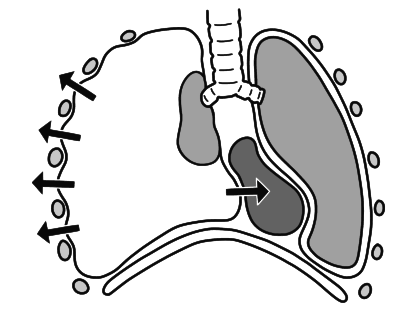

Εξέλιξη του πνευμοθώρακα σε πνευμοθώρακα υπό τάση:

Πνευμοθώρακας που έχει προκληθεί από διαπεραστικό τραύμα ή σπασμένο πλευρό, μπορεί να λειτουργήσει σαν βαλβίδα μίας κατευθύνσεως, επιτρέποντας στον αέρα από το περιβάλλον να μπει στον υπεζωκοτικό χώρο, αλλά όχι να βγει.

Όσο μαζεύεται αέρας, η πίεση αυξάνεται, και ο πνεύμονας θα καταρρεύσει. Η αυξανόμενη πίεση σπρώχνει την καρδιά και τα μεγάλα αιμοφόρα αγγεία προς την ανεπηρέαστη πλευρά. Αυτό ονομάζεται πνευμοθώρακας υπό τάση. Καθώς η πίεση αυξάνεται, η πίεση στις μεγάλες φλέβες μειώνει την επιστροφή αίματος στην καρδιά, και μπορεί να προκαλέσει αποφρακτικό σοκ. Αν η πίεση αυξηθεί τόσο που το αίμα να μην μπορεί να επιστρέψει στην καρδιά, το άτομο παθαίνει καρδιακή ανακοπή.